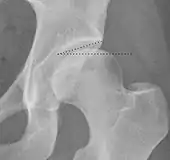

Crowe classification

In 1979 Dr. John F. Crowe et al. proposed a classification to define the degree of malformation and dislocation. Grouped from least severe Crowe I dysplasia to most severe Crowe IV.[13] This classification is very useful for studying treatment results.

Rather than using the Wiberg angle because it makes it difficult to quantify the degree of dislocation they used 3 key elements to determine the degree of subluxation: A reference line at the lower rim of the "teardrop", junction between the femoral head and neck of the respective joint and the height of the pelvis (vertical measurement). They studied anteroposterior pelvic x-rays and drew horizontal lines through the lower rim of a feature called "teardrop". The distance between this line and the middle lines of the junction between femur head and neck gave them a measure of the degree of femur head subluxation. They further established that a "normal" diameter of the femur head measures 20% of the height of the pelvis. If the middle line of the neck-head junction was more than 10% of the pelvis height above the reference line they considered the joint to be more than 50% dislocated.[13]

The following types resulted:[13]

Class | Description | Dislocation |

Crowe I | Femur and acetabulum show minimal abnormal development. | Less than 50% dislocation |

Crowe II | The acetabulum shows abnormal development. | 50% to 75% dislocation |

Crowe III | The acetabula is developed without a roof. A false acetabulum develops opposite the dislocated femur head position. The joint is fully dislocated. | 75% to 100% dislocation |

Crowe IV | The acetabulum is insufficiently developed. Since the femur is positioned high up on the pelvis this class is also known as "high hip dislocation". | 100% dislocation |